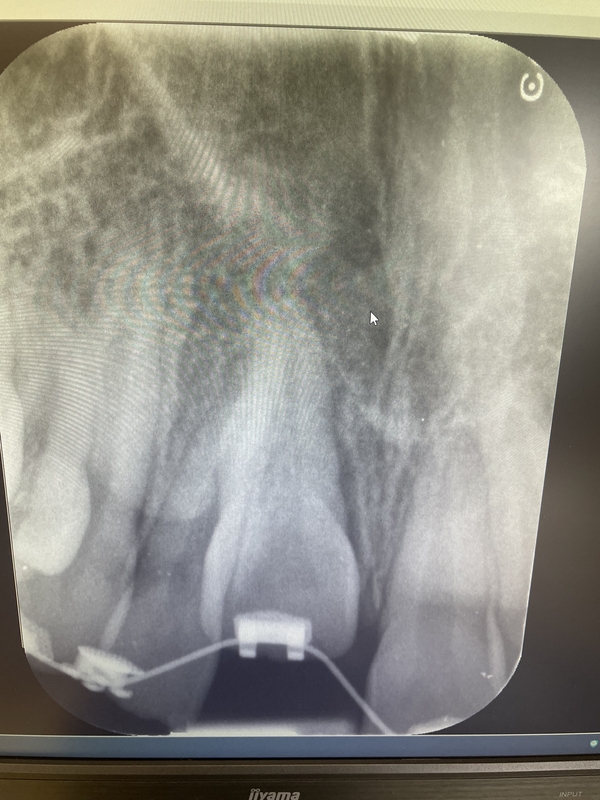

Case 5 – Dental Trauma

Severe Intrusion during braces